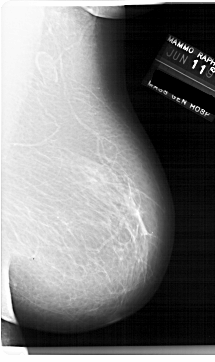

A_1920_1.RIGHT_MLO

RIGHT_MLO LINES 6871 PIXELS_PER_LINE 4081 BITS_PER_PIXEL 12 RESOLUTION 43.5 NON_OVERLAY